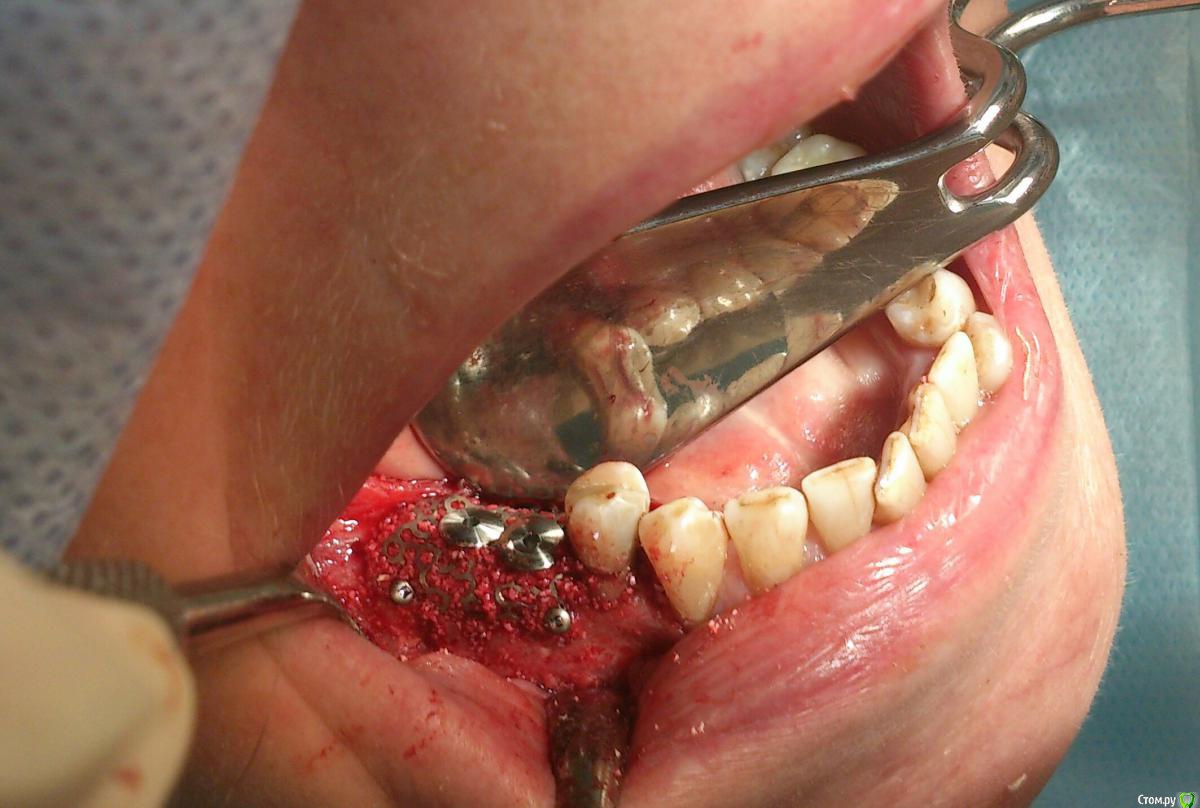

andrey_1965 Опубликовано 21 декабря, 2015 Поделиться Опубликовано 21 декабря, 2015 Ну как результат ?1.-диэпителизация подворот лоскута очень удобно,но опасно для резбы через неделю.язычно-механическая травма через 10 дней через 3недели. На временных доформирую рельеф.2. вроде ничего нештатного через 2недели A-PRF через 5недель убрал все,закрыл мембраной A-PRF две поперек,одна в доль через неделю через 13дней через 21день. Следующий осмотр будет на сроке 5 недель(думаю все сравняется) 3. через неделю 2недели 3недели,на дистальных отмываю помойку4 недели Ссылка на комментарий